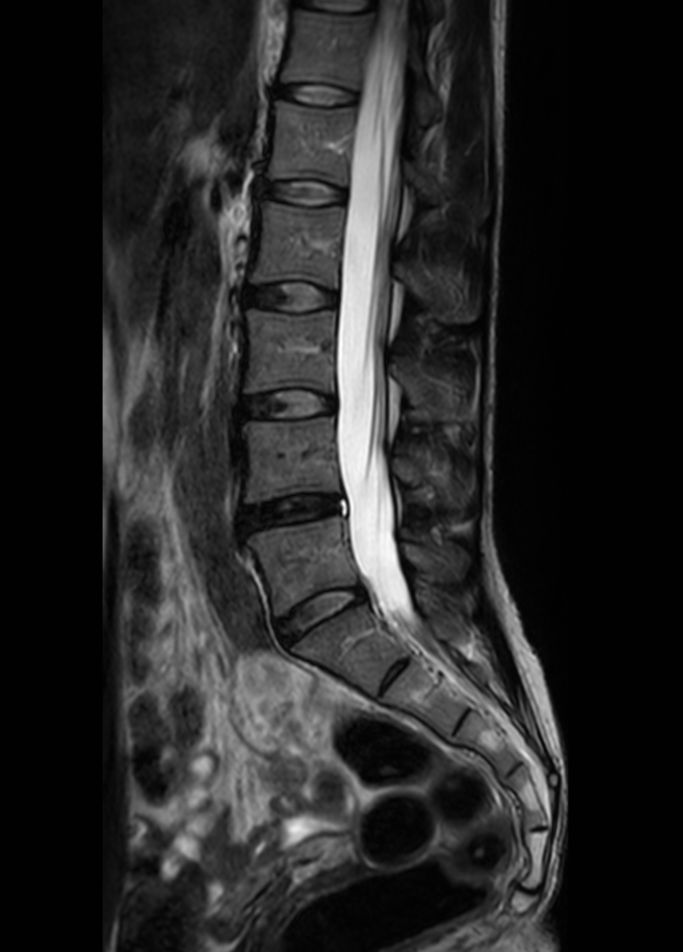

Lumbar Plexus imaging

• Clinical Application